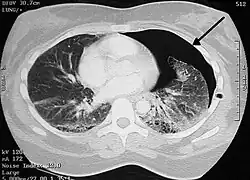

Pneumotórax (do grego, pneumo ar; thorax peitoral) é uma emergência médica causada pela presença de ar entre as membranas que envolvem os pulmões (cavidade pleural) e gera um pulmão colapsado (atelectasia) disfunção nos alvéolos, causada pelo extravasamento de líquido da pleura. Pode afetar um ou ambos pulmões e causar dificuldade para respirar (dispneia).[1]

A cavidade pleural é o espaço entre as duas pleuras, que normalmente só deve ser liso e conter líquido pleural. Os pulmões permanecem expandidos na cavidade pleural devido à pressão negativa que varia de -3 a -12 mmHg durante todo o ciclo respiratório. Portanto, a pressão intrapleural negativa contrapõe-se à retração elástica dos pulmões.

A formação do derrame gasoso, após a ruptura pleural, eleva a pressão intrapleural e o pulmão tende ao colapso. Um pneumotórax de grandes proporções ou um pneumotórax aberto tende a aumentar progressivamente a pressão intrapleural ocasionando o colapso do pulmão, desvio do mediastino, compressão das veias, queda do débito cardíaco e hipotensão arterial.

Diagnóstico

Casos leves podem ter poucos sinais e sintomas sendo necessário um exame de imagem, enquanto casos graves devem ser tratados imediatamente com tubo de drenagem intercostal por baixo da axila (no "triângulo seguro") sem exame de imagem. Ao exame físico de um caso moderado ou grave, podemos verificar:[6]